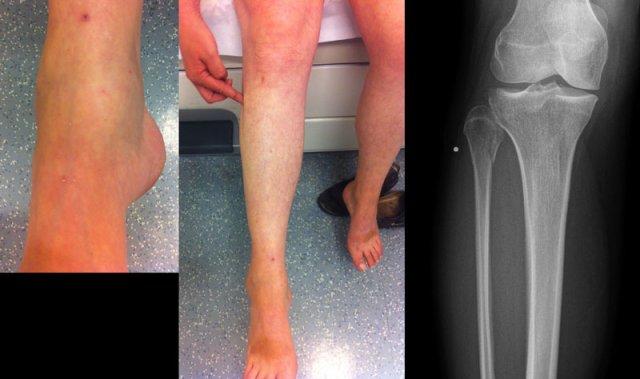

Đây là hình ảnh của một ca bệnh cực kỳ khó.

Bệnh nhân nữ bị bong gân cổ chân và đau cả hai bên trong và ngoài.

Bệnh nhân được bác sĩ đa khoa chuyển đến khoa Chẩn đoán Hình ảnh.

Kỹ thuật viên chụp các tư thế chuẩn gồm thẳng (AP), Mortise và nghiêng, sau đó trình bày cho bác sĩ X-quang, người đã khá băn khoăn khi đọc phim.

Hãy đọc hình ảnh trước, sau đó tiếp tục đọc phần giải thích.

Các dấu hiệu bao gồm:

-

Phù nề phần mềm cả hai bên trong và ngoài (mũi tên đỏ).

Đặc biệt, phù nề phía trong nên gợi ý khả năng chấn thương xoay ngoài – sấp (Weber C). - Đường thấu quang trên tư thế Mortise (mũi tên đen) và tư thế nghiêng. Dấu hiệu này nên gợi ý gãy tertius.

Bác sĩ X-quang quyết định chỉ định CT trước để xác định xem có thực sự có gãy tertius hay không.

Tiếp tục xem hình ảnh CT và bạn sẽ ngạc nhiên.

Hãy cuộn qua các lát cắt.

Thật đáng ngạc nhiên khi một mảnh tertius lớn như vậy lại rất khó nhìn thấy trên phim X-quang.

Cũng lưu ý phù nề phần mềm phía trong gợi ý đứt dây chằng bên trong (mũi tên).

Bạn có thể đoán được đây là loại chấn thương gì không?

Phù nề phần mềm phía trong và gãy tertius đều là dấu hiệu của chấn thương Weber C hoặc chấn thương xoay ngoài – sấp.

Do không thấy gãy xương mác trên phim X-quang cổ chân, phải có gãy xương mác cao.

Khi khám lâm sàng, có phù nề nhẹ phía trong và mặc dù bệnh nhân không than đau ở vùng cao hơn của cẳng chân, vẫn có điểm đau khi ấn vào xương mác.

Vị trí này được đánh dấu và phát hiện đường gãy.

Ca bệnh này minh họa tầm quan trọng của phù nề phần mềm phía trong cũng như dấu hiệu gãy tertius.

Theo phân loại Lauge Hansen, chúng ta có thể kết luận rằng bệnh nhân này đầu tiên bị đứt dây chằng bên trong (giai đoạn 1), tiếp theo là đứt dây chằng chày mác trước (giai đoạn 2), gãy xương mác cao (giai đoạn 3) và cuối cùng là bong mắt cá sau, tức là chấn thương xoay ngoài – sấp (PE) giai đoạn 4.

Trong phẫu thuật, cổ chân được xác định là không vững và vít cố định khớp chày mác đã được đặt vào.

Có chỉ định cố định gãy mắt cá sau vì mảnh gãy chiếm hơn 25% diện khớp của đầu dưới xương chày.

Bệnh nhân này bị lật cổ chân và bất thường duy nhất được thấy trên tư thế nghiêng.

Tổn thương này được cho là bong điểm bám mắt cá sau.

Biết rằng đây có thể là dấu hiệu duy nhất của gãy Weber C cao, các phim X-quang bổ sung đã được chụp.

Tiếp tục xem hình ảnh cẳng chân.

Có thể thấy một đường gãy xương mác cao kín đáo (mũi tên).

Chẩn đoán cuối cùng là gãy Weber C hoặc theo phân loại Lauge Hansen: chấn thương xoay ngoài – sấp giai đoạn 4.